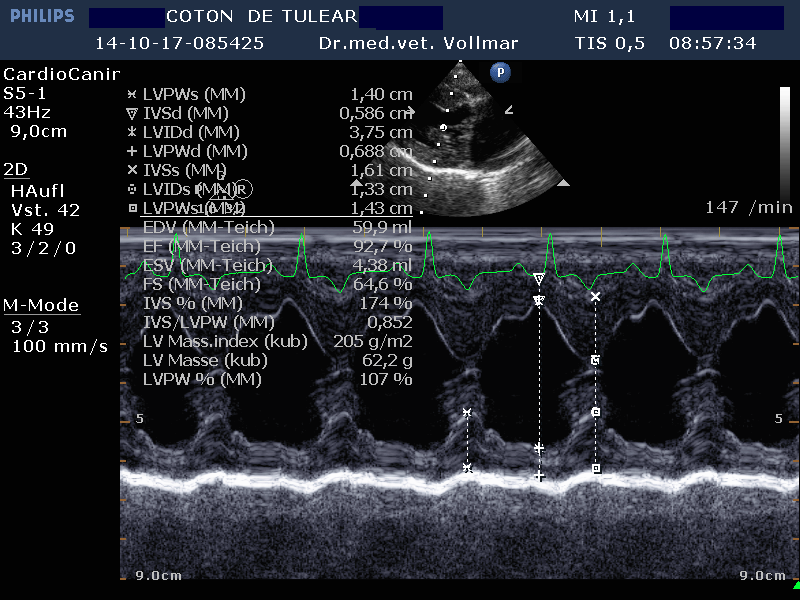

Degenerative Mitralklappeninsuffizienz (MI)

Die degenerative Mitralklappeninsuffizienz (MI) stellt beim Hund die Hauptursache für ein kongestives Herzversagen und kardial bedingten Tod dar. Im Krankheitsverlauf vergrößert sich mit zunehmender Schwere der Klappeninsuffizienz zunehmend der linke Vorhof und das diastolische Ventrikelvolumen nimmt zu, während das systolische Ventrikelvolumen erst mit nachlassender Kontraktilität bei Entwicklung einer Volumenüberlastungskardiomyopathie zunimmt. Bei kleineren Hunden unter 15 kg Körpergewicht ist dies oft erst später im Krankheitsverlauf der Fall, bei größeren Hunden über 15 kg hingegen häufig früher.

Nach derzeitigem Kenntnisstand ist bei MI eine Medikation immer erst dann sinnvoll, wenn bereits eine Herzvergrößerung vorliegt.

Am sichersten kann die Größe der einzelnen Herzabteilungen und der Schweregrad einer AV-Klappeninsuffizienz mit Hilfe der Echokardiografie beurteilt werden. Die Messung der Vorhofgröße vorzugsweise im 2D-Bild korreliert zuverlässig mit dem Ausmaß der MI. Mittels verschiedener Doppler- und Farbdoppler-Analysemethoden kann die Größe der Lücke in der Mitralklappe bestimmt und das regurgitierte Blutvolumen ermittelt werden.